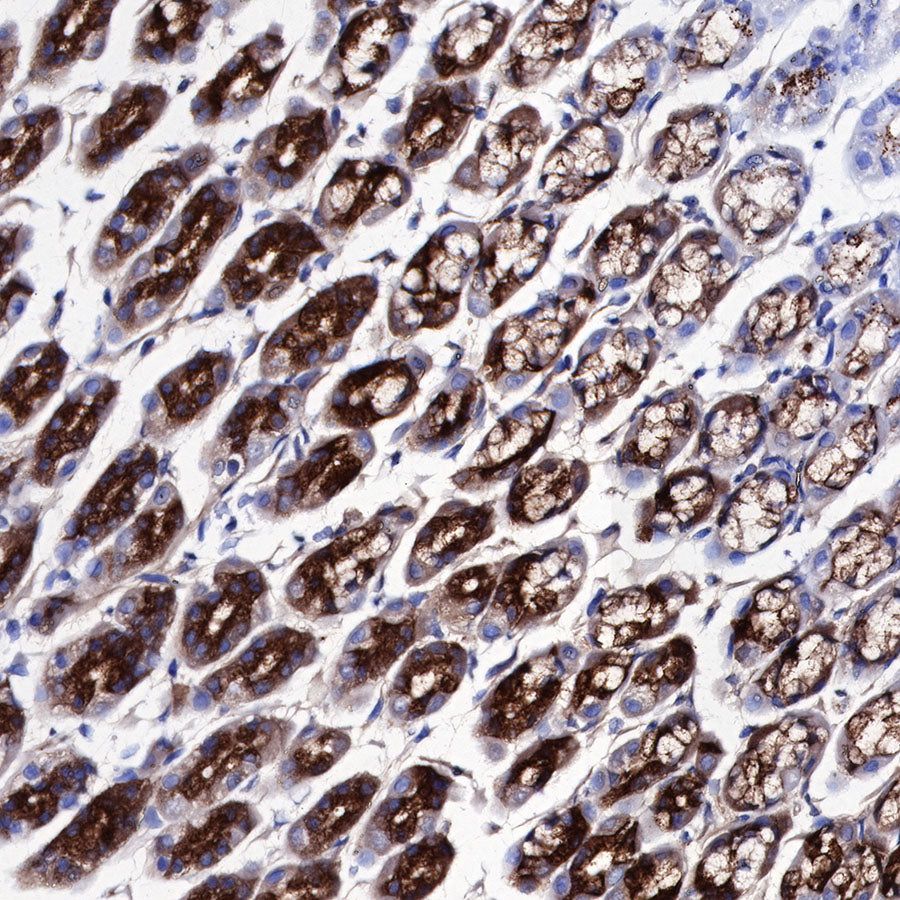

Immunohistochemistry

IHC shows positive staining in paraffin-embedded human stomach. Anti-PG II/PGC antibody was used at 1/1000 dilution, followed by a HRP Polymer for Mouse & Rabbit IgG (ready to use). Counterstained with hematoxylin. Heat mediated antigen retrieval with Tris/EDTA buffer pH9.0 was performed before commencing with IHC staining protocol.